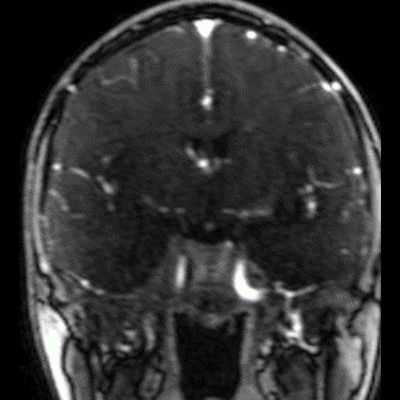

14 yaş, K

Baş ağrısı ve sağda abdusens felci

Neurosarcoidosis manifesting as cavernous sinus syndrome in systemic sarcoidosis

Sağ kavernoz sinüste kontrastlanan ICA yı çevreleyen daraltan yumuşak doku değerleri mevcuttur.Sağ parahiler bölgede lenfadenopati veya kitle lezyonu ile uyumlu olabilecek görünüm mevcuttur.Ayırıcı tanıda Nazofarink Ca metastazı,lenfoma,sarkaidoz,wegener granulomatozu düşünüle bilir.Çocuk hasta olduğu için daha çok lenfoma olarak düşündüm